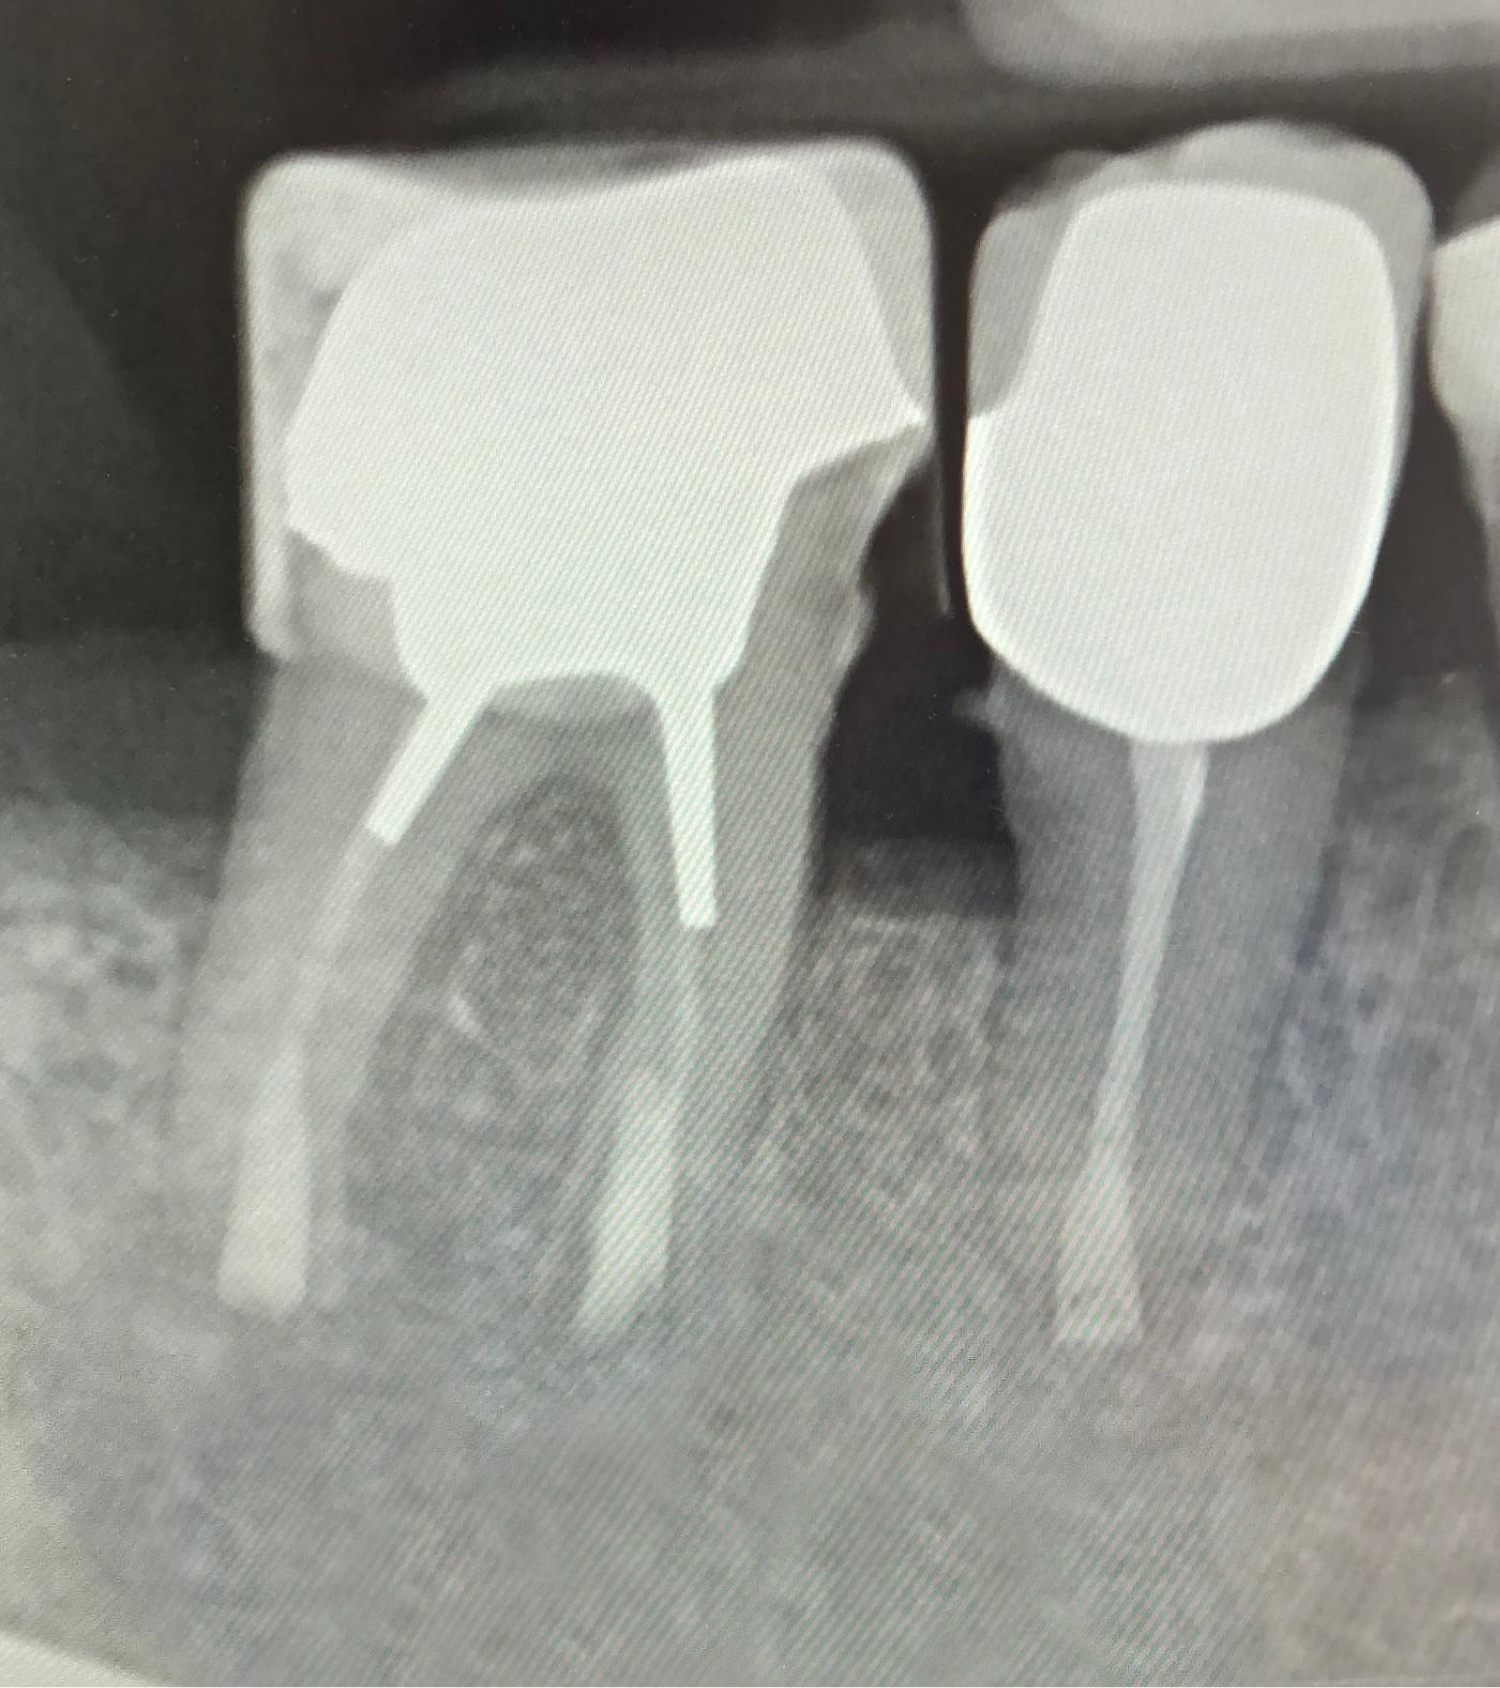

Zahnärztliches Röntgenbild mit mehreren Backenzähnen – Darstellung von Wurzelkanalbehandlungen und Füllungen zur Diagnostik in der Zahnklinik Nordhorn

Nachher